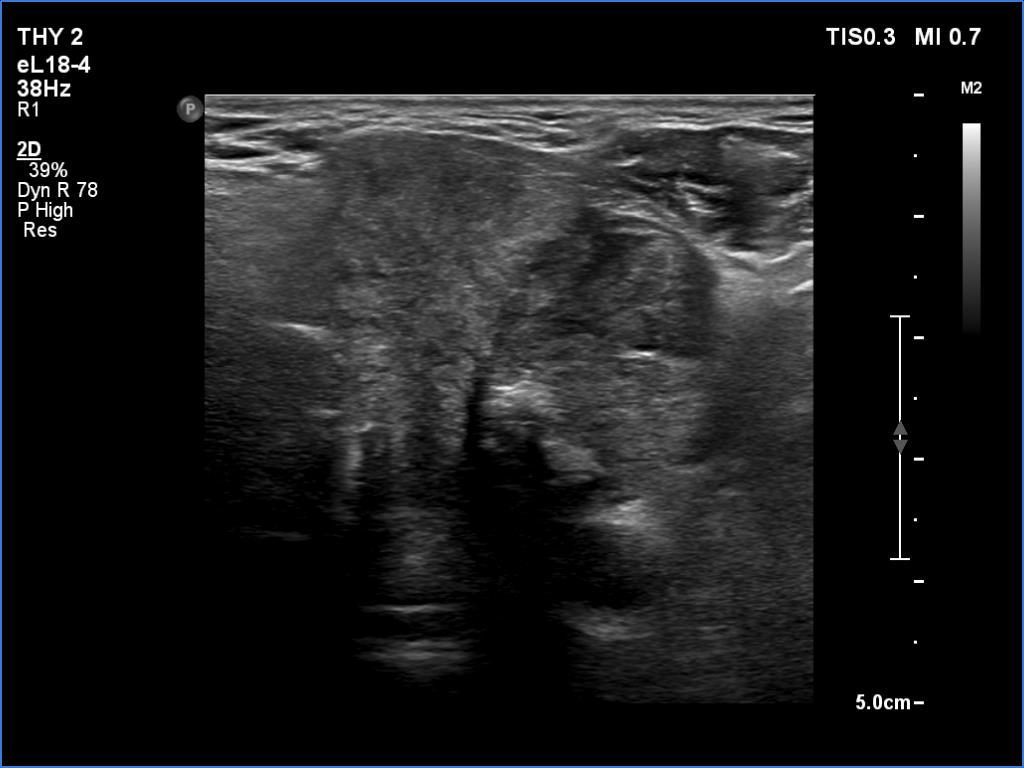

Elastography - case 1260 (ultrasonographic picture 8)

Left lobe, anther longitudinal view. The tumor has irregular borders.